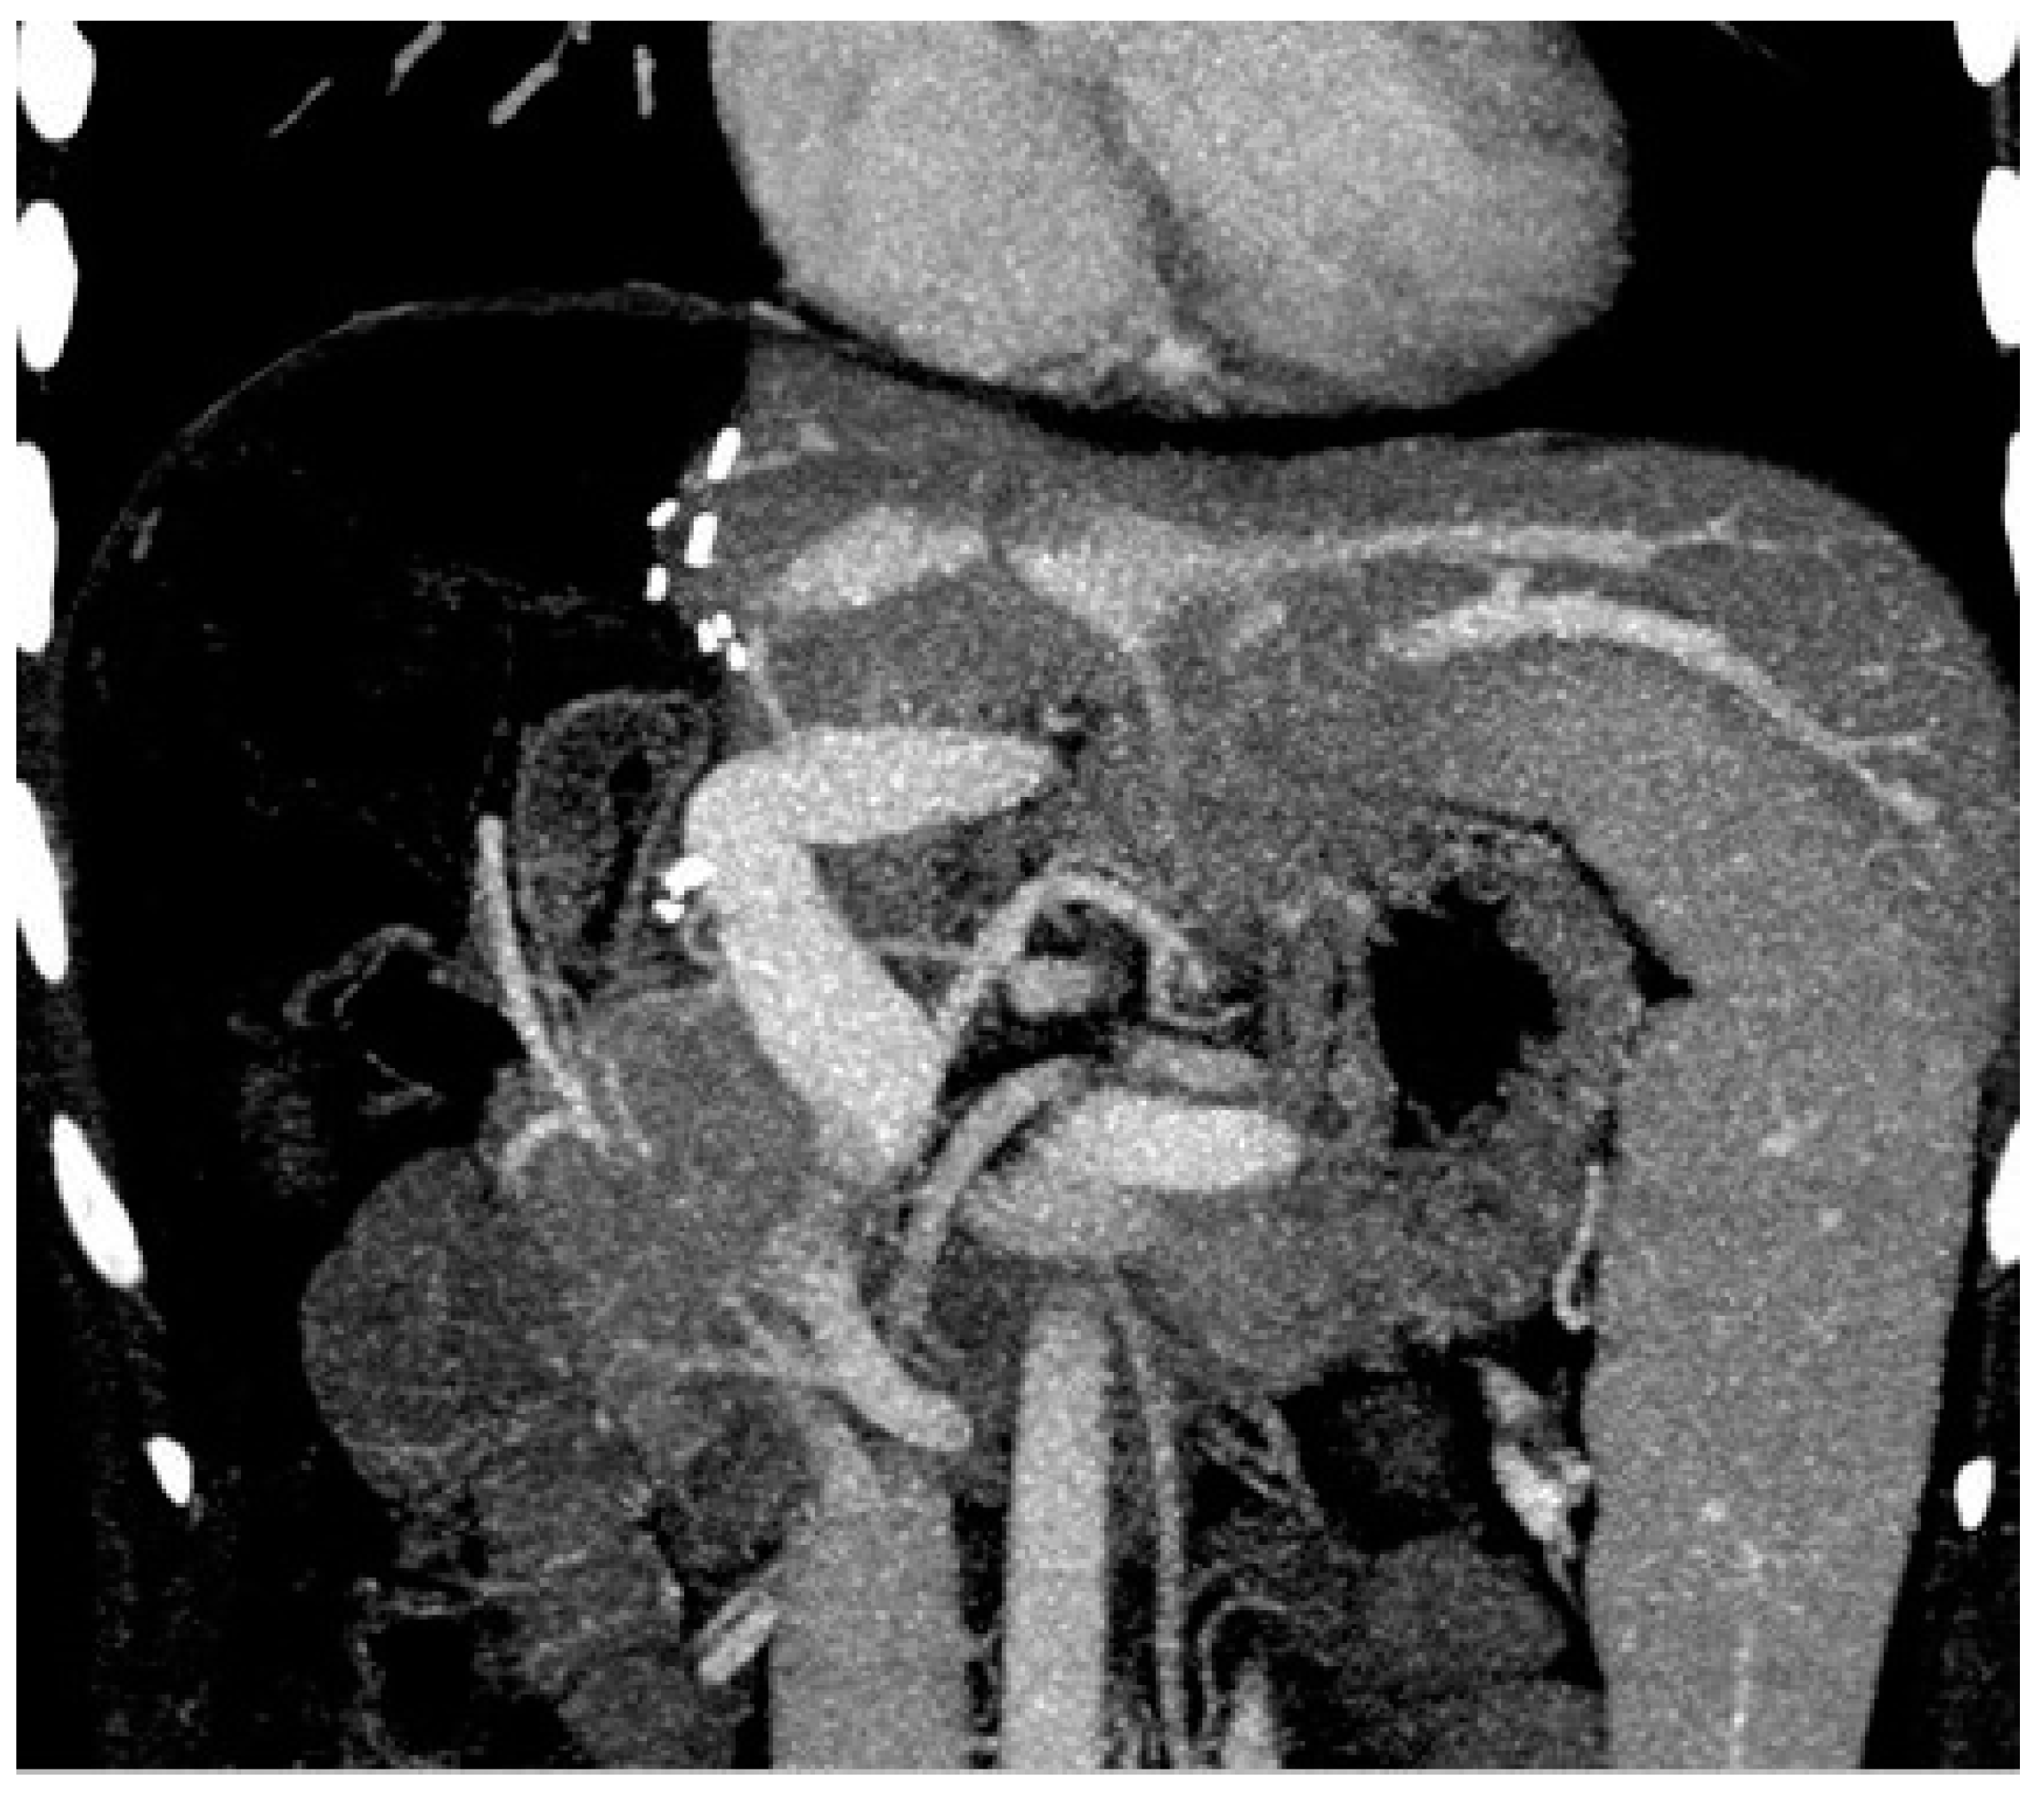

Figure 5.

The coronal reformatted computed tomography imaging shows that the portal vein reconstructed with the elbow patch technique is patent.